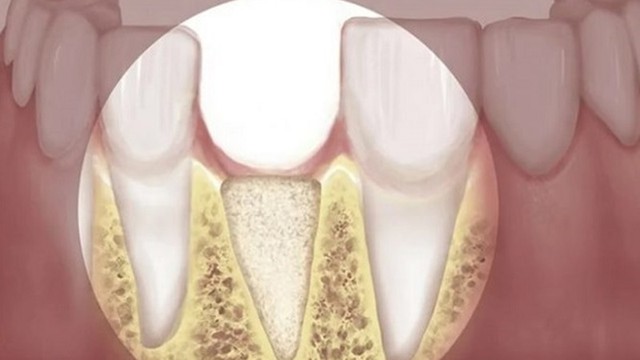

/https://cms-prod.s3-sgn09.fptcloud.com/nhung_anh_huong_ve_suc_khoe_cua_tieu_xuong_ham_d_Hx_Vo_1680281519_b2d7772113.jpg)

Tiêu xương hàm là một bệnh răng miệng nguy hiểm, thường xảy ra sau khi mất răng, gây ra tiêu biến của xương chân răng. Nếu không được điều trị kịp thời, bệnh có thể dẫn đến các vấn đề như lệch khớp cắn, méo miệng và mất chức năng ăn nhai, gây ảnh hưởng nghiêm trọng đến thẩm mỹ và sức khỏe của bệnh nhân.